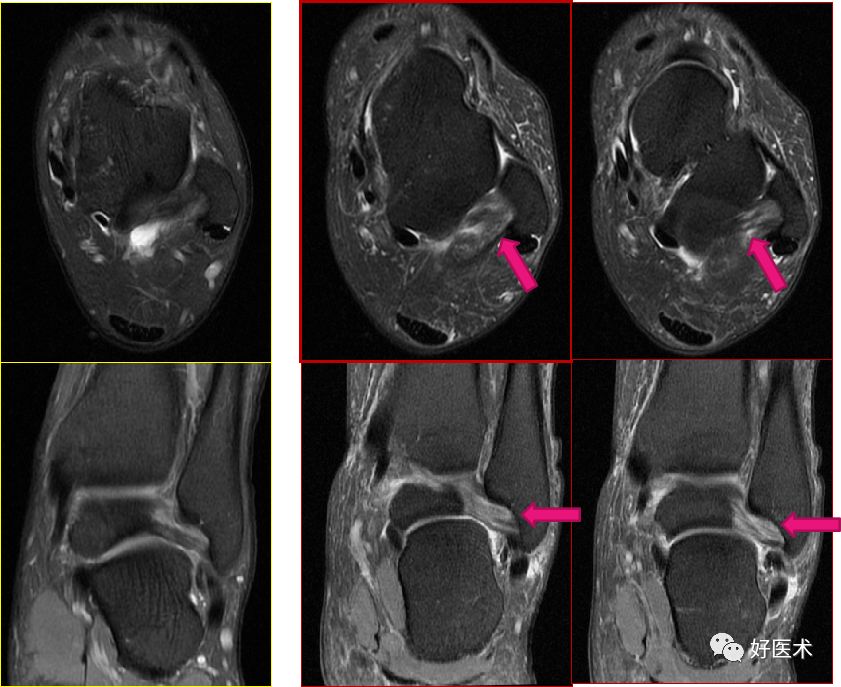

三角韧带

踝关节内侧韧带又称三角韧带,为强劲的三角形纤维束。上方附着于内踝尖及其前后缘;浅层纤维为胫舟部,前行附着于舟骨粗隆,部分与跟舟足底韧带的内侧面融合;中间部为胫跟部,下方附着于载距突;后部为胫距后部,纤维附着于至距骨内侧面和内侧结节。

三角韧带撕裂